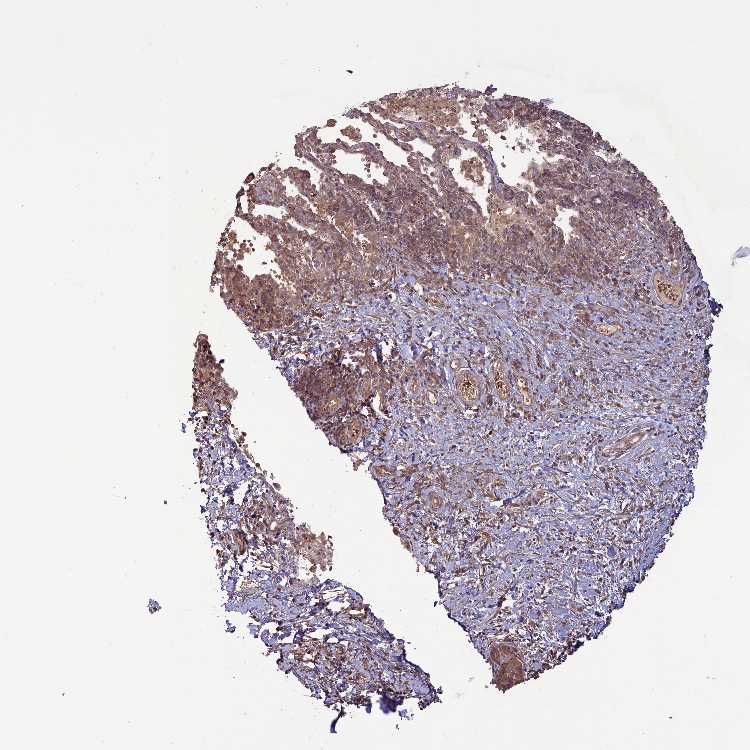

SOFT TISSUE 1 - Antibody stainingi

Antibody staining in the annotated cell types in the current human tissue is reported as not detected, low, medium, or high, based on conventional immunohistochemistry profiling in selected tissues. This score is based on the combination of the staining intensity and fraction of stained cells.

Each image is clickable and will lead to virtual microscopy that enables deeper exploration of all samples and also displays staining intensity scores, fraction scores and subcellular localization as well as patient and tissue information for each sample.

Antibody HPA041501Antibody HPA041736

Chondrocytes Not detectedMedium

Fibroblasts LowMedium

Peripheral nerve LowMedium